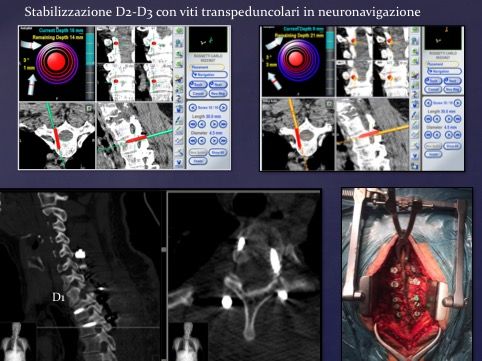

Durante il mio percorso lavorativo specialistico ho eseguito più di 1000 procedure chirurgiche riguardanti la patologia cerebrale (tumori, malformazioni vascolari, ematomi intracranici spontanei o post-traumatici, idrocefalo, fratture della teca cranica e del massiccio facciale), la patologia degenerativa e traumatica a carico della colonna vertebrale (ernie del disco cervicali, toraciche, lombo-sacrali, fratture a carico della colonna vertebrale e sacro-iliache, tumori spinali, stabilizzazioni vertebrali con tecnica open e percutanea mini-invasiva con particolare esperienza nella tecnica di neuronavigazione spinale), la patologia del sistema nervoso periferico, mediante interventi per sindrome del tunnel carpale al polso e del tunnel cubitale al gomito. Ho esperienza nel trattamento del M. di Parkinson non responsivo a terapia farmacologica attraverso la procedura neurochirurgica funzionale di Deep brain Stimulation (DBS).